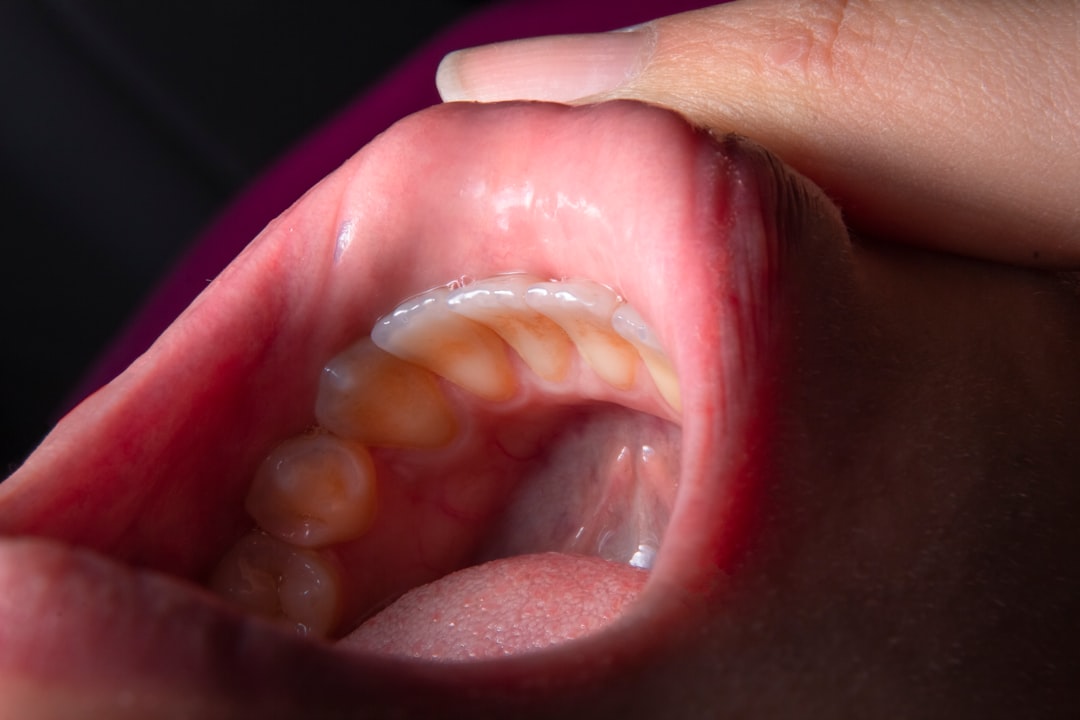

편도염의 정확한 진단을 위해서는 몇 가지 방법이 필요합니다. 먼저, 의사는 환자의 병력과 증상에 대한 자세한 이야기를 듣습니다. 그 다음, 물리적 검사를 통해 목과 편도를 살펴보고 염증이 있는지 확인합니다. 이 과정에서 목젖이 붓는 이유가 편도염인지 판단할 수 있습니다.